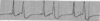

Interpret this EKG

Non-conducted PAC in Bigeminal rhythm